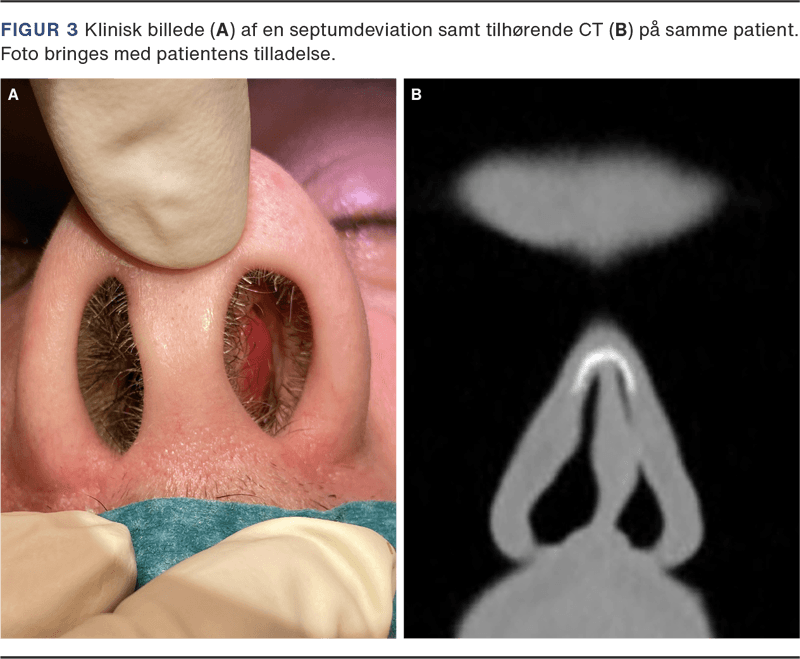

Ved inspektion nedefra vurderes columellas position i forhold til alae nasi samt septums placering bag columella (Figur 3 A + B). Næsetippens styrke og stabilitet vurderes ved palpation.